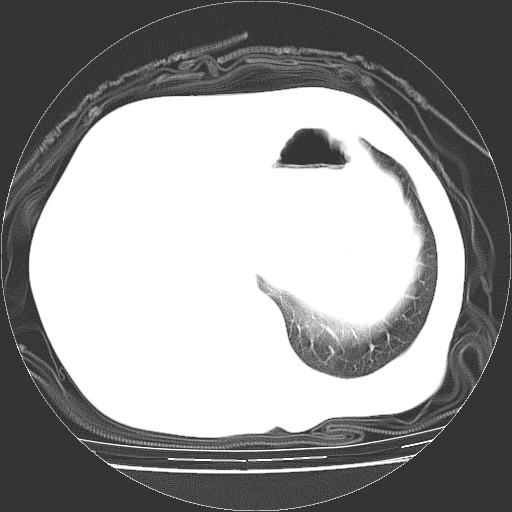

标题: CT23991:女,72岁,咳嗽、憋气一周。 [打印本页]

女,72岁,咳嗽、憋气一周,十年前曾患肺结核及胸膜结核。

右侧毁损肺,右侧纵隔疝

右侧毁损肺,右侧纵隔疝,左肺代偿!

1.右侧损毁肺伴胸膜钙化,2.左肺小结节灶,良性可能大,注意复查。3.肝脏左叶囊肿。4.先天性一侧肺不发育待出外(右侧胸廓无明显塌陷)。对比原片应该非常有帮助。

右侧肺毁损,左肺代偿性肺气肿,纵隔疝。